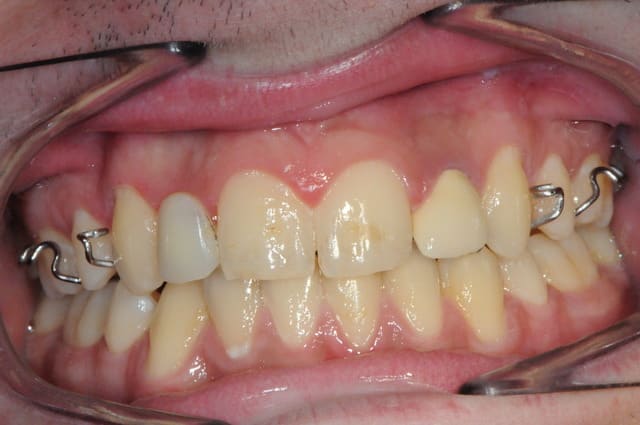

Salut D57,

Ton cas est intéressant mais hormis la concavité vestibulaire, à mon avis largement rattrapable avec une expansion,

2 autres pièges attirent mon attention, c'est typique des agénésies des latérales.

1: Absence d'alignement des collets, à gérer impérativement en cours de chirurgie, sinon dent trop courte et inesthétique.

2: espace MD trop étroit à vue d'oeil, attention au type d'implant.

Si le col implantaire est trop large (sup à 3 mm de diam ) tu aura une compression gingivale et disparition des papilles.

Au fait,

il faudra penser à lui enlever les restes de composite.

C'est terrible cette manie des ortho, ils ne s'appliquent jamais pour enlever les restes de colle à la fin des traitements.